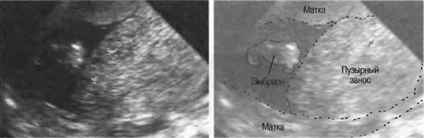

Пузырчатый занос, или молярная беременность, представляет собой аномалию, при которой в матке формируется не нормальный эмбрион, а скопление пузырьков, заполненных жидкостью. Это состояние возникает в результате нарушения процесса оплодотворения и последующего развития плода. В норме после оплодотворения яйцеклетка начинает делиться и развиваться, но при пузырчатом заносе происходит аномалия, в результате которой вместо нормального плода образуются пузырьки, представляющие собой атипичные ткани.

Существует два основных типа пузырчатого заноса: полная и частичная молярная беременность. При полной форме отсутствует нормальная эмбриональная ткань, и все ткани, которые развиваются, представляют собой аномальные пузырьки. Частичная форма подразумевает наличие как аномальных, так и нормальных тканей, но в этом случае также не формируется жизнеспособный плод.

Диагностика с помощью УЗИ: Одним из основных методов диагностики пузырчатого заноса является ультразвуковое исследование. На УЗИ можно увидеть характерные “пузырьки” в матке, которые представляют собой скопления аномальных тканей. Это позволяет врачам быстро и точно определить наличие заболевания.

Для исследования пузырчатого заноса применяются анализы крови, вагинальное обследование и УЗИ. Благодаря современным технологиям, с помощью ультразвука можно легко определить наличие такого заболевания. После проведения операции и лечения, врачи наблюдают за состоянием женщины и проводят разные обследования.

Чтобы увидеть, как выглядит пузырчатый занос, можно посмотреть фото в интернете. Обычно на ультразвуковом исследовании четко видны пузыри, которые располагаются внутри матки. Как можно понять, при таких изменениях в органе, развитие здорового плода не может происходить.